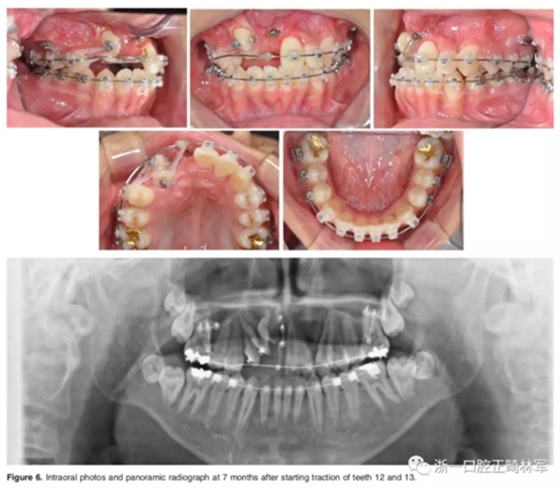

一期手術(shù)主要是牽引側(cè)切牙和尖牙:于上頜前牙區(qū)唇側(cè)作切口,翻全厚瓣;腭側(cè)面較小;在尖牙唇側(cè)、側(cè)切牙腭側(cè)粘扣掛結(jié)扎絲牽引,通過一輔助鈦板及樹脂等連接至弓絲上;采用閉合式導(dǎo)萌技術(shù),將皮瓣復(fù)位縫合,僅結(jié)扎絲穿過粘膜;2周內(nèi)軟組織得以愈合,牽引開始。先通過正畸力,近中移動(dòng)側(cè)切牙,遠(yuǎn)中移動(dòng)尖牙。10個(gè)月后,阻生牙牙冠萌出,側(cè)切牙、尖牙的易位得以矯正。

二期手術(shù)主要是牽引中切牙:于上頜前牙區(qū)腭側(cè)作切口,翻全厚瓣,在切牙唇側(cè)粘扣掛結(jié)扎絲牽引;軟組織愈合后,牽引開始。為施加合適的垂直向力,在下頜前牙區(qū)放置C型管,掛橡皮筋牽引。14個(gè)月后,切牙牙冠萌出。使用mini管代替托槽,對切牙、尖牙進(jìn)行矯治;矯治過程采用輕力,0.014-in鎳鈦絲。